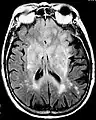

Axial fluid-attenuated inversion recovery MRI image demonstrating tumor-related infiltration involving both temporal lobes (Short arrow), and the substantia nigra (Long arrow).